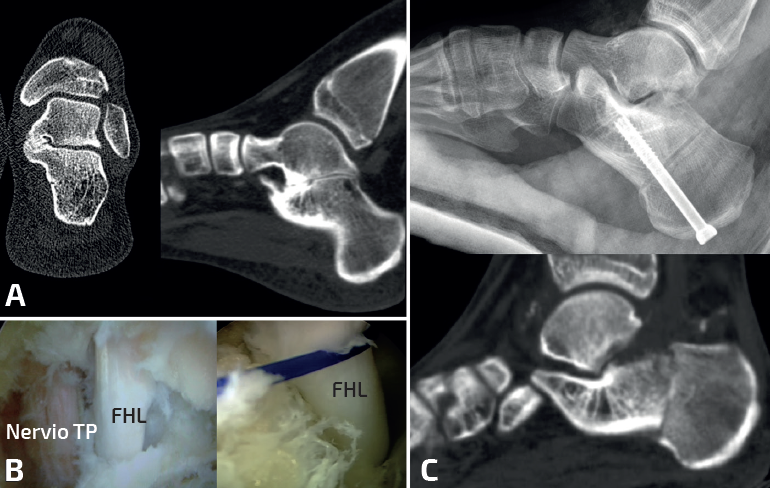

Cirugía de la coalición calcaneoastragalina(10)

La resección de la CA es más compleja, los resultados tras la cirugía de resección son difíciles de estimar debido a que estas coaliciones son muy variables en términos de localización, tamaño y grado de deformidad del pie(9,16). Se consideran resecables las coaliciones que afectan menos del 50% de la superficie de la carilla media en relación con el área de superficie de la carilla posterior y sin datos radiográficos de artrosis, mientras que se consideran irresecables las coaliciones que afectan a más del 50% de la superficie articular. Las opciones terapéuticas son:

- Resección aislada de la coalición: indicada en casos de CA resecable y valgo del retropié menor de 16°. Mediante un abordaje medial sobre el sustentáculo tali se resecan aproximadamente 10 mm entre ambos huesos. Es importante respetar el sustentáculo tali, resecando más superficie del astrágalo que del calcáneo. A veces, es difícil identificar la coalición, sobre todo si es completamente ósea. La proyección radioscópica intraoperatoria de Harris puede ayudar a su localización, mientras que la TC intraoperatoria, las guías de corte con impresiones 3D o las técnicas de navegación están en desarrollo. La resección se considera completa cuando se consigue movilizar la articulación subastragalina y se visualiza la carilla articular posterior. Es importante interponer algún material como grasa para evitar reosificaciones. Las técnicas endoscópicas también están ganando popularidad, porque se visualiza y se reseca mejor la coalición que afecta a la carilla posterior, pero tienen una importante curva de aprendizaje y no se recomiendan en las coaliciones que afectan a la carilla media y anterior(13,14)(Figuras 5, 6 y 7).

- Resección de la coalición asociada a corrección del pie plano valgo: indicada en casos de CA resecable y valgo del retropié mayor de 16°. La resección de la coalición no restaura la morfología del pie, incluso puede empeorar el valgo del retropié. Se emplean técnicas como el alargamiento de la columna externa u osteotomía de deslizamiento medial del calcáneo, mejorando de forma significativa la función, la sintomatología y las imágenes radiográficas del pie. Si tras la corrección del valgo se objetiva supinación del antepié se asocia una osteotomía de flexión plantar de la primera cuña (Figura 8). La mayoría de los autores realizan ambos procesos simultáneamente. Otros autores recomiendan realizar ambos procedimientos en dos tiempos quirúrgicos separados en el tiempo, por las mismas razones que se han comentado anteriormente. Al igual que en las coaliciones CE, si existe una deformidad en valgo aumentada, preferimos realizar la cirugía simultáneamente.